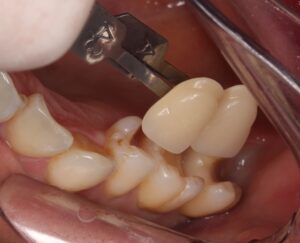

7番目の歯の詰め物を削っていくと、

中から茶色い虫歯が出てきました。

茶色い虫歯が内部で広がっています(*_*)

6番目の歯から見てみると、

歯と歯の間から虫歯になっており、

表面から虫歯を削っていくと、

歯の間も黒く虫歯の侵入があるのが分かります。

う蝕検知液で染色されないところまで丁寧に虫歯を取ります。

まだ茶色いところがありますが、

赤く染色されないので、着色であると分かります。

こちらを削ってしまうと、歯の削りすぎになります。

虫歯でないところは残しましょう。

虫歯が入っていたところは、色素が沈着し茶色く歯に色が付いてしまうことが良くあります。